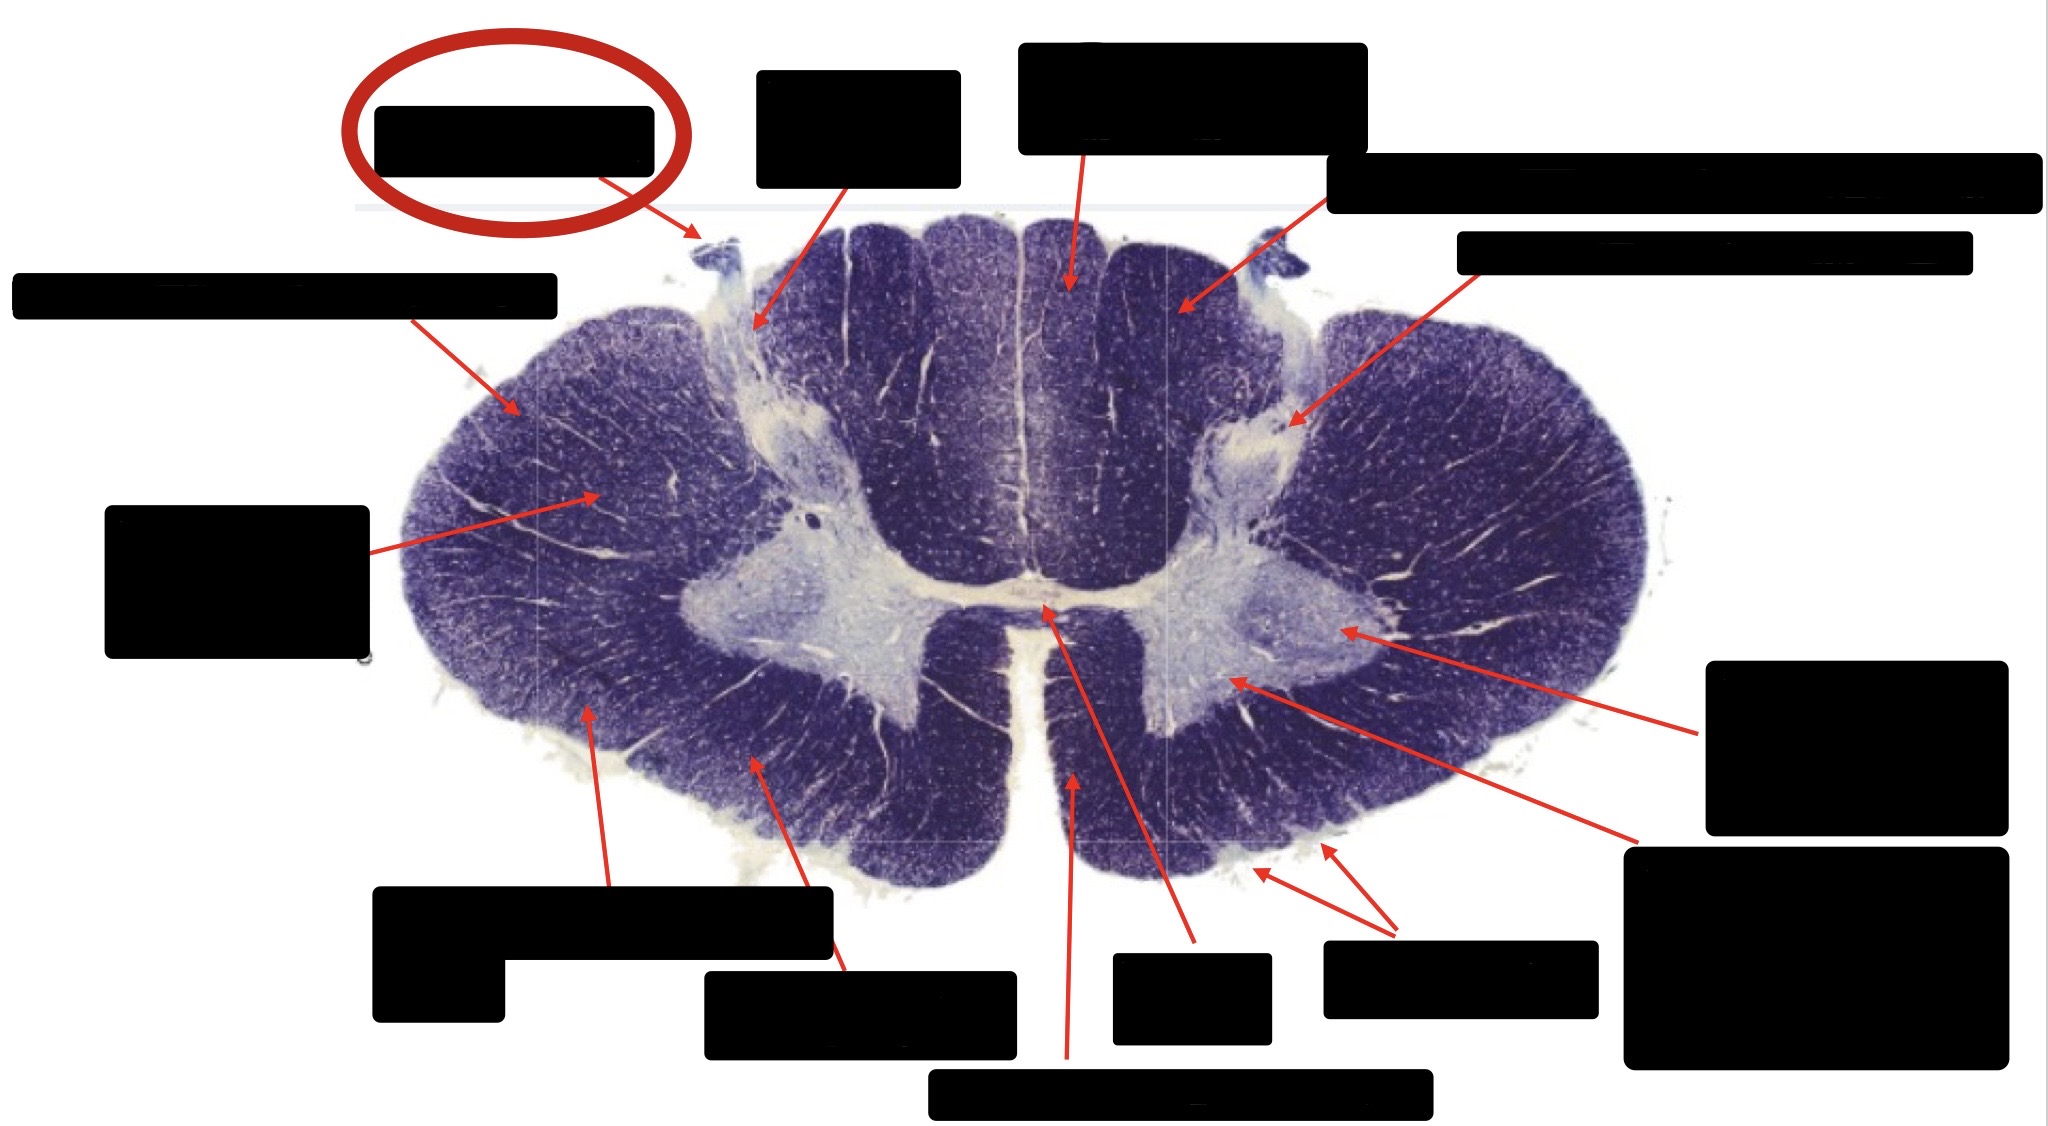

Posterior Column

Large Fiber Entry Zone

Posterior Spinocerebellar Tract

Clarke’s Nucleus

Anterior Spinocerebellar Tract

Ventral Root Fibers

Central Canal

Lissauer’s Tract & Small Fiber Entry Zone

Substantia Gelatinosa

Lateral Corticospinal Tract

Spinothalamic Tract

Anterior Horn Motor Neurons (Distal Muscles)

Anterior Horn Motor Neurons (Proximal Muscles)

Dorsal Rootlet

Lateral Horn

Spinothalmic Tract